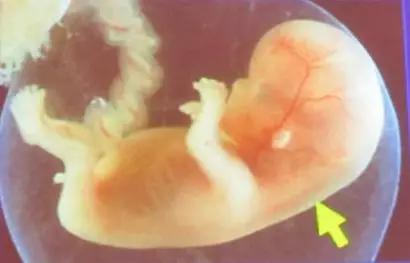

什么是胎儿NT?

就是箭头所指这个地方的厚度啦!

胎儿NT是指在胎儿11周~13周+6天(头臀长应不小于45mm,及不大于84mm)利用超声检查到的胎儿颈后皮下积液,为什么要在这个期间检查呢?11周之前因为胎儿太小,而过了14周,过多的液体可能被胎儿正在发育的淋巴系统吸收,结果不准确。